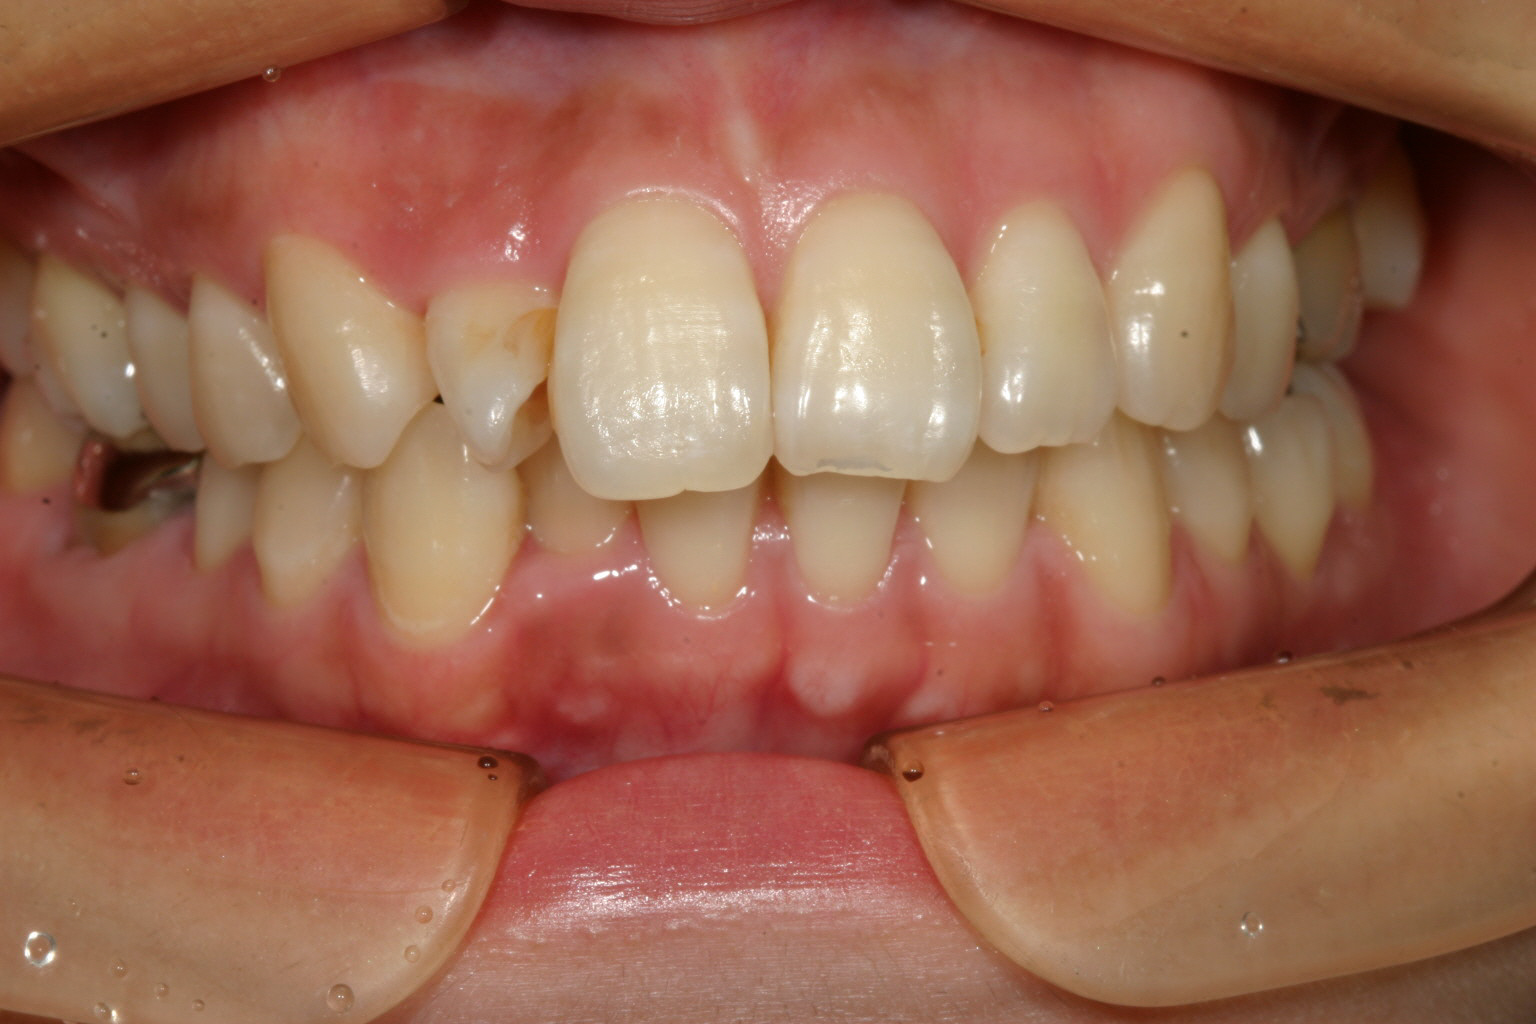

アーチフォームは綺麗ですが右上の2番目がちょっと横向いてます。

下顎の右下の2番目が少し中に入ってます。

少し出っ歯観が気になりますね~